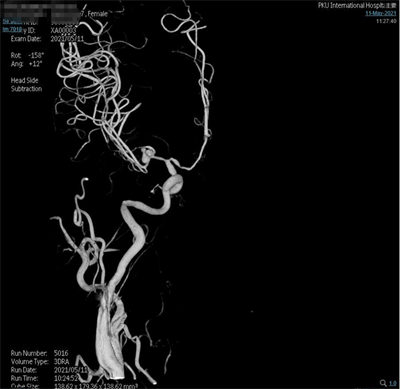

夹闭后造影

患者气管插管全麻满意后,双侧腹股沟区常规消毒铺巾,右侧腹股沟韧带下方股动脉搏动最强点下方约1.5cm处穿刺,右股动脉行Seldinger穿刺,置入5F动脉鞘,超滑泥鳅导丝携带5F单弯造影管分别行双侧颈总动脉、双侧颈外动脉及双侧椎动脉正侧位造影,造影见:右侧大脑中动脉M1分叉处2个动脉瘤;左侧大脑中动脉M1分叉处2个动脉瘤,其中一个可见子瘤。仰卧位头右偏。常规碘酒及酒精消毒后铺巾。取左额颞弧形切口,逐层切开头皮及皮下,切开颞肌筋膜及颞肌,筋膜下入路,颞肌翻向下方,暴露颅骨。颅骨钻1孔,铣刀铣下骨瓣约5X3cm大小。硬膜张力不高。分离蝶骨嵴两侧硬脑膜,进一步咬除蝶骨嵴。硬膜四周悬吊。弧形剪开硬脑膜,向前翻转固定。显微镜下锐性分离侧裂,打开蛛网膜,放出脑脊液后脑组织压力下降,显露颈内动脉,大脑中动脉及其分支,见动脉瘤位于大脑中动脉M1段。分离动脉瘤两侧粘连蛛网膜,显露动脉瘤前后端中动脉及其分支,分离瘤蒂两侧,上1枚临时阻断夹阻断左侧大脑中动脉,后更换另1枚临时阻断夹阻断左侧大脑中动脉,上3枚德国进口动脉瘤夹夹闭2个动脉瘤瘤蒂,调整后夹闭满意,松阻断夹,术中动脉瘤未破裂。造影显示中动脉及其分支通畅。创面止血,覆盖止血纤维及凝血酶海绵,生理盐水冲洗清亮,脑组织搏动良好。护士清点棉条、棉片、纱布及器械无误,严密缝合硬膜。骨瓣复位,3枚钛片固定。逐层缝合颞肌、颞肌筋膜、皮下及头皮各层。包扎固定纱布,酒精消毒术前贴膜,将患者头左偏,取右额颞弧形切口,逐层切开头皮及皮下,切开颞肌筋膜及颞肌,筋膜下入路,颞肌翻向下方,暴露颅骨。颅骨钻2孔,铣刀铣下骨瓣约5X5cm大小。硬膜张力不高。分离蝶骨嵴两侧硬脑膜,进一步咬除蝶骨嵴。硬膜四周悬吊。弧形剪开硬脑膜,向前翻转固定。显微镜下锐性分离侧裂,打开蛛网膜,放出脑脊液后脑组织压力下降,显露大脑中动脉及其分支,见动脉瘤位于大脑中动脉M1段,分离动脉瘤两侧粘连蛛网膜,显露动脉瘤前后端中动脉及其分支,分离瘤蒂两侧,第3枚临时阻断夹阻断右侧大脑中动脉上一枚德国进口动脉瘤夹夹闭瘤蒂,调试后夹闭满意,松阻断夹,术中动脉瘤未破裂。造影显示中动脉及其分支通畅。创面止血,覆盖止血纤维及凝血酶海绵,生理盐水冲洗清亮,脑组织搏动良好。护士清点棉条、棉片、纱布及器械无误,严密缝合硬膜。骨瓣复位,3枚钛片固定。逐层缝合颞肌、颞肌筋膜、皮下及头皮各层。手术顺利,术中出血约700ml,回输自体血140ml。手术时间较长,患者带气管插管安返神经外科-ICU病房。

脑动脉造影(外院,2021-5-10):双侧大脑中动脉分叉多发动脉瘤。